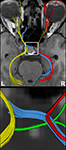

Figure 4

shows the components of the entire visual pathway for a single subject (#1) in both hemispheres (top view). Despite the caution to reduce false-positive tracks, it was impossible to avoid fiber tracks that travel along the optic nerve and jump over to a neighboring eye muscle, namely the medial or lateral musculus rectus, the course of which closely parallels that of the optic nerve. On the other hand, because of the absence of susceptibility artifacts, we could differentiate fiber bundles that cross the optic chiasm. As shown in Figure 5

we separately identified fibers connecting the right eye, more precisely the axons of the eye’s ganglion cells, with the right and left LGN, as well as fibers connecting the left eye with the left and right LGN. The approach distinguishes the lateral retinal fibers from the nasal retinal fibers that cross the chiasm and enter the opposite optic tract. Finally, the fiber bundles of the optic radiation are visualized in Figure 6

. The anatomic courses of Meyer’s loop, the central bundle, and the dorsal bundle that all connect the LGN with the primary visual cortex closely follow the expected outline as depicted in Figure 1 and described in Section “Introduction”.

Figure 4. (Top) Bi-hemispheric reconstructions of the optic nerve and tract (red) as well as of the optic radiation (yellow). (Bottom) Dissection of the optic radiation into Meyer’s loop (yellow), central bundle (green), and dorsal bundle (blue). R, right, L, left.

Figure 5. (Top) Separation of right- and left-hemispheric fibers in the optic nerve and optic tract. (Bottom) Magnification of fiber tracks crossing the optic chiasm: tracks from the left eye to the left (yellow) and right LGN (blue), tracks from the right eye to the left (green) and right LGN (red). R, right, L, left.